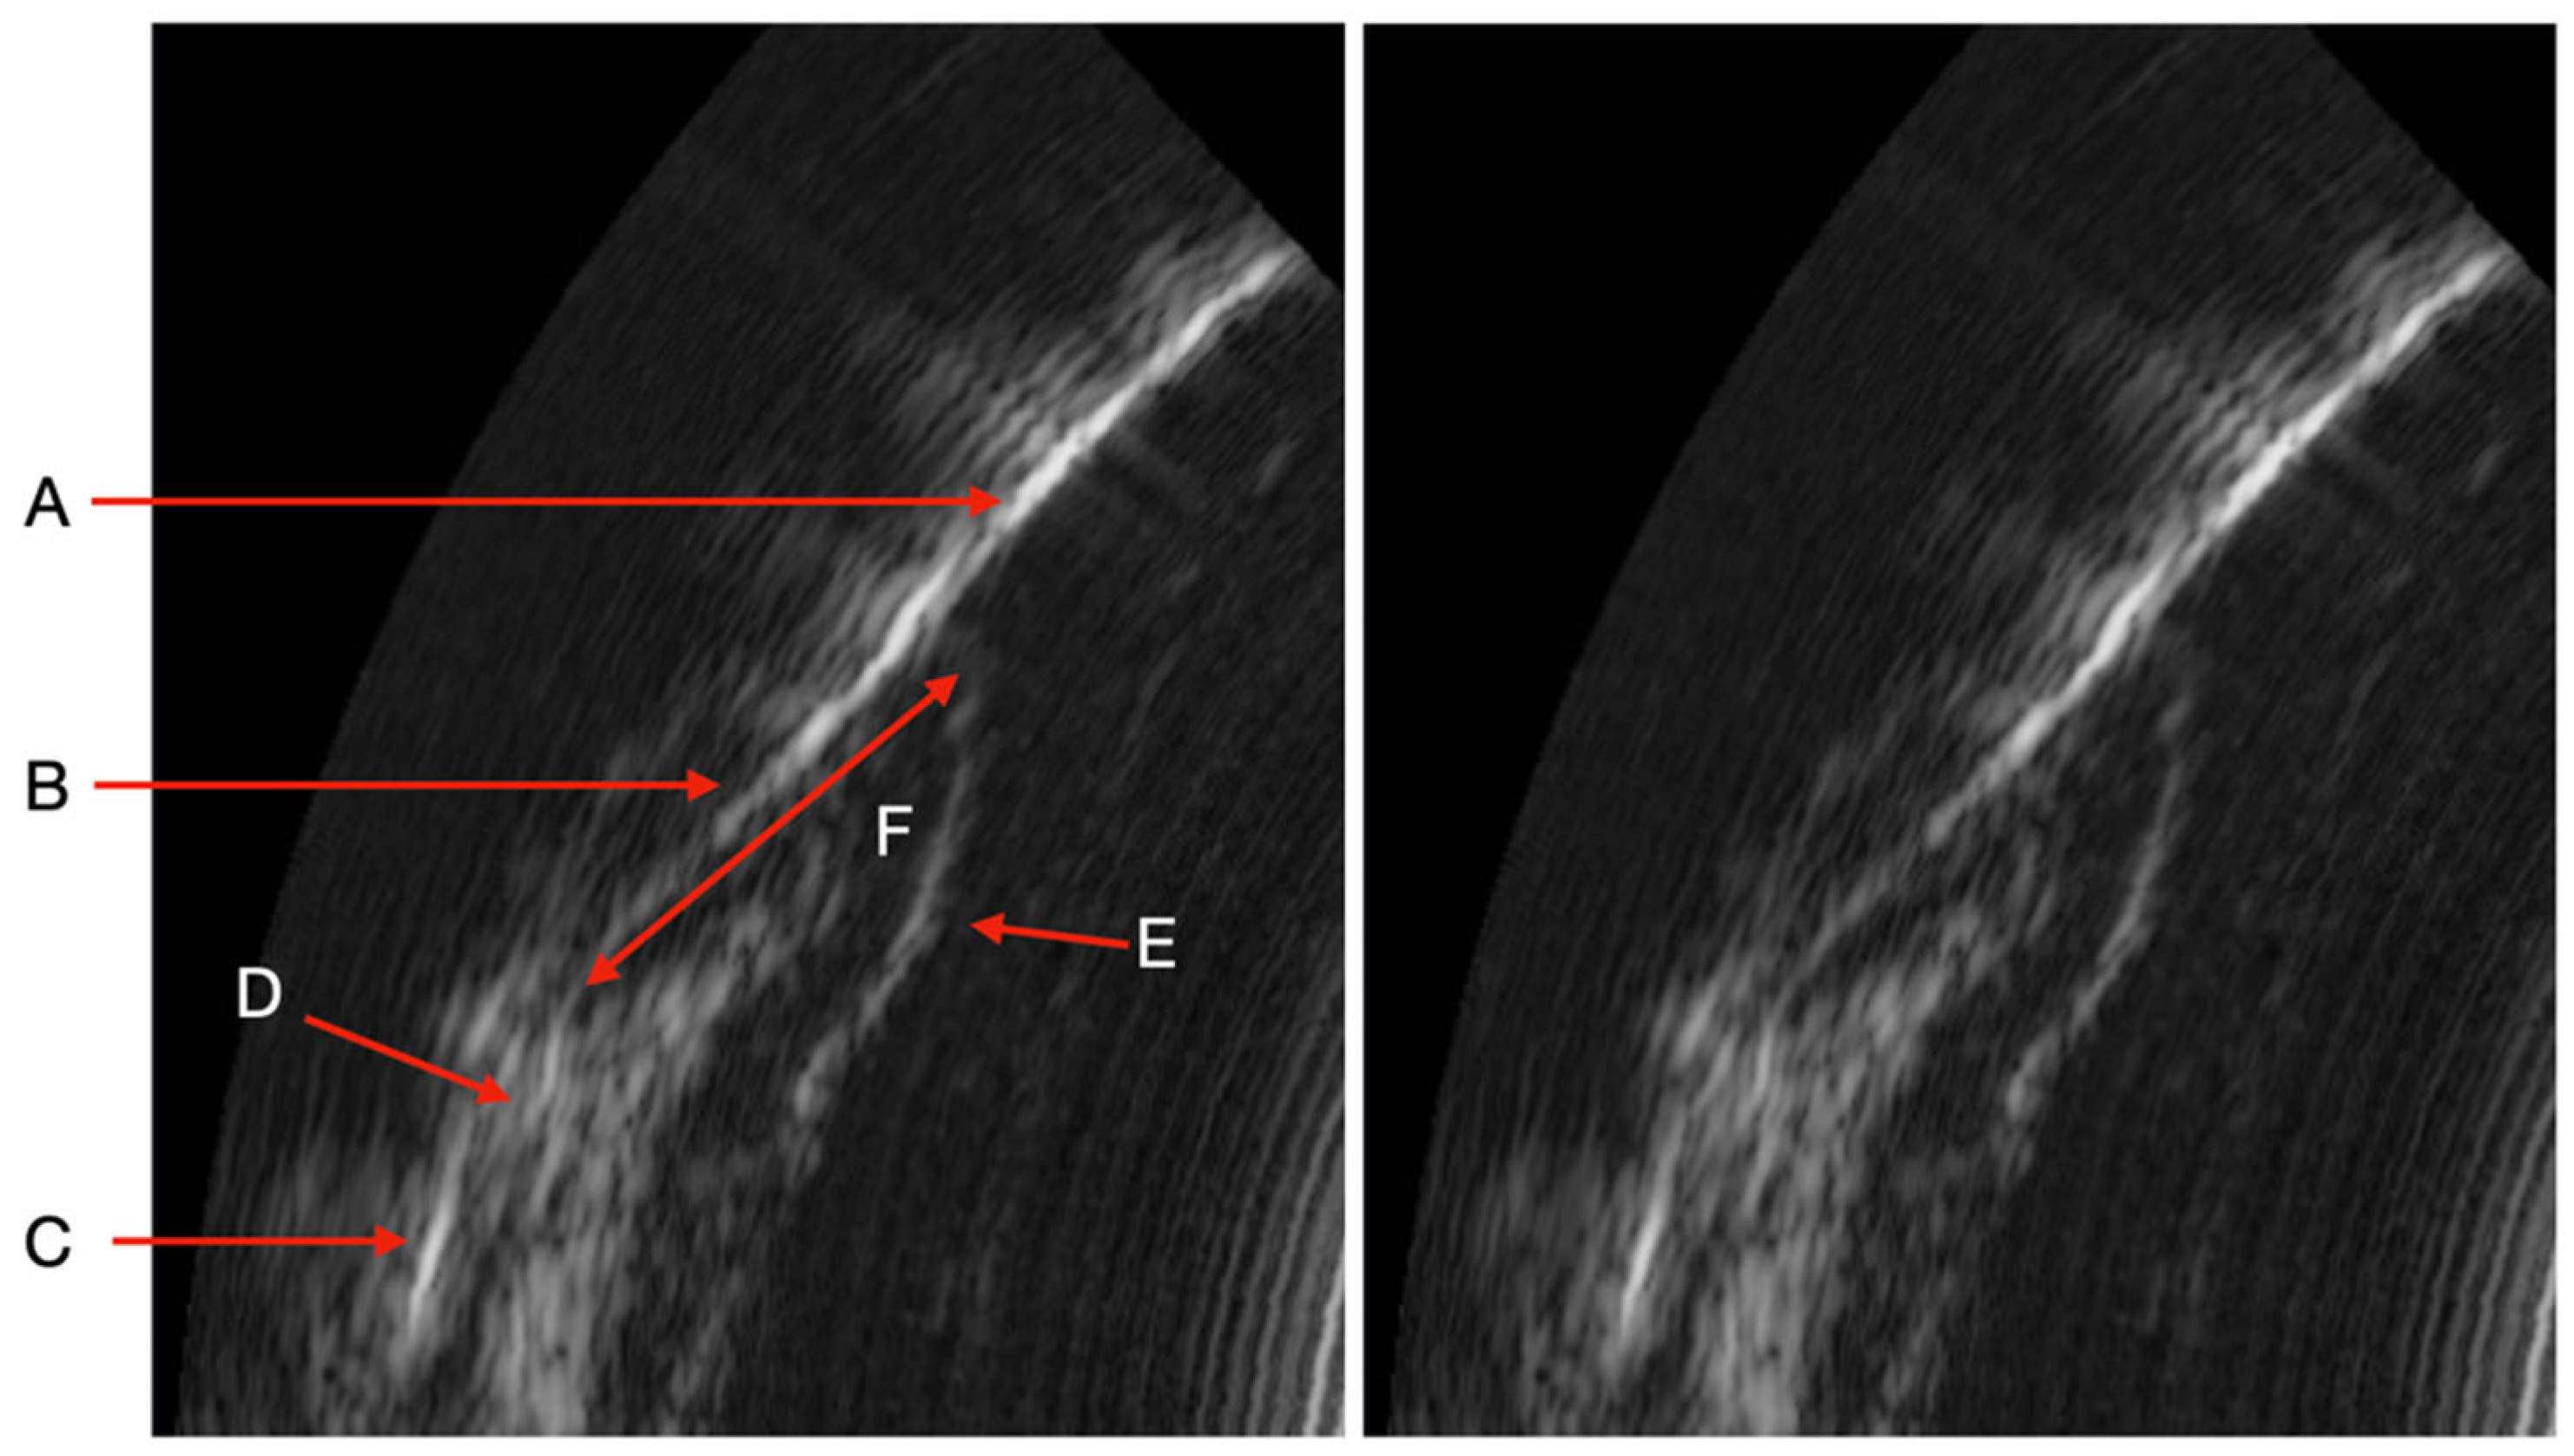

Image obtained by the US device (A: Enamel. B: Cemento-enamel junction. C: Alveolar bone crest. D: Connective tissue attachment. E: Keratinized free gum. F: Sulcus/pocket area).

The ultrasound (US) probe captures real-time images (US probing). All periodontal structures are clearly visible in the image under physiological and pathological conditions. Periodontal tissues (enamel, cemento-enamel junction, alveolar bone crest, connective tissue attachment, keratinized free gum, sulcus/pocket area) can be easily identified after a short period of learning to read ultrasound images. These structures need to be identified so that the AI algorithm can then automatically measure the sulcus area. All periodontal structures appear in Figure 2.

During the study, we observed many variations in ultrasound images depending on the clinical situation (inflammatory area, presence of visible calculus, edema, spontaneous bleeding, normal situation). Indeed, the images can reveal the presence of inflammation in the deep gingival tissues. Sub-gingival calculus can also be visible. The image quality is also different because of the variation in the ultrasound signal [13]. The same is true for subgingival calculus which can also be objectified on the ultrasound images. Although many of these elements appear in the image, AI currently struggles to differentiate pocket depths from surrounding structures in certain clinical contexts. These structures need to be identified and characterized for more precise training of the AI (Figure 4)

It should be noted that we can observe several clinical situations that can give a bias in measuring the periodontal pocket automatically by AI (Figure 2). The detection of significant inflammation in the image can greatly influence the outcome in the difference in pocket depth measurements obtained with the AI algorithm and the manual probe. Indeed, there are situations where the boundary between the inflammation image and the bottom of the pocket is not clear. This is explained by the absence of connective tissue visible on the image. In these specific cases, as it is trained today, the AI algorithm measures the depth of the periodontal pocket associated with the amount of inflammation. In other situations, the boundary is clearly visible on the image and the distinction between the periodontal pocket and the inflammation is easily identifiable by AI. This type of image alerts the clinician to the reality of the pocket. Indeed, can we say whether the pocket measured with the manual probe is really the one to be considered if, in addition, a deep inflammatory zone is already present on the ultrasound imaging. In addition, other images show the presence of supra or subgingival calculus. The same is true for the presence of deep calculus, at the bottom of the periodontal pocket, which can impact the measurement obtained by the AI algorithm of the area (current AI algorithm training specifications). Although the presence of tartar does not represent a diagnostic element in the determination of periodontal disease, the possibility of being able to identify the presence of tartar from the initial clinical examination (to choose the scaling strategy), at the end of the instrumentation (to evaluate the effectiveness of the procedure), as well as during the maintenance phases, represents a considerable impact in terms of saving time, procedures, costs and, above all, reducing fatigue and wear of the dentist.